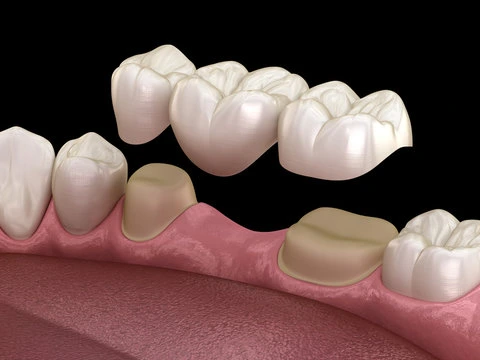

Crown & Bridges

Crowns and bridges restore damaged or missing teeth. Crowns cover and protect weak teeth, while bridges fill gaps using adjacent teeth for support. Made from durable, aesthetic materials like porcelain or zirconia. Improves function and appearance. Long-lasting solution for better oral health.